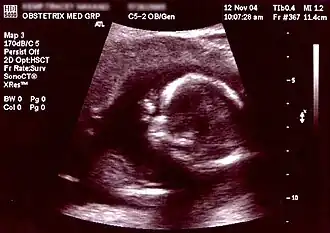

Ecografia às 16 semanas de gestação. O círculo branco entre o centro e o lado direito é a cabeça do feto, estando a face voltada para a esquerda. Imaginando os ponteiros de um relógio, às 10 horas é visível a testa, às 7 horas a orelha esquerda e às 9 horas a mão direita a tapar os olhos.